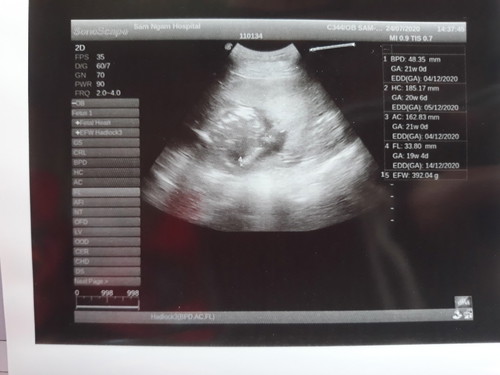

อยากรู้น้ำหนักลูก ปกติไหมค่ะ เห็นหมอบอกน้องตัวเล็กค่ะ 20week

EFW 392.04 g. ค่ะ ก็ไม่เล็กนะแม่